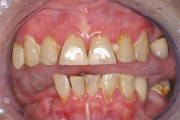

Kõige tavalisem kaebus sülje hüpofunktsiooni korral on püsiv, terve päev kestev suukuivus. Selline seisund nõuab sagedat joomist. Inimesed ärkavad tihti keset öö ja on sunnitud võtma klaasi vett endaga voodisse. Tuleb eristada aga neid, kes ärkavad põhiliselt hommikul, sest suukuivuse Loe edasi »